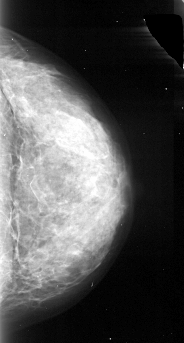

A_1092_1.LEFT_CC

LEFT_CC LINES 4036 PIXELS_PER_LINE 2326 BITS_PER_PIXEL 16 RESOLUTION 42 OVERLAY